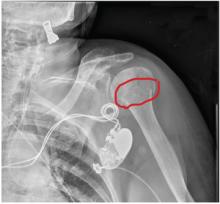

A 90-year-old woman is transferred to your facility from an outside hospital for evaluation of an intracranial hemorrhage secondary to a fall. The patient normally resides in a nursing home and has dementia. She was reportedly ambulating with her walker when she tripped and fell forward. In addition to dementia, her medical history is significant for sick sinus syndrome, for which she has a pacemaker. She also has hypertension and degenerative joint disease. Examination reveals an elderly female who is alert but very confused. Her vital signs are normal. She has moderate swelling and bruising on the left side of her forehead and left orbit. Her pupils react well. As you examine her, you note her unwillingness to use or move her left arm. When you inquire, she states, “It hurts.” Close examination of the left upper extremity shows no obvious deformity or swelling. She does have some tenderness over the left shoulder. You order a radiograph of the left shoulder (shown). What is your impression?

The radiograph demonstrates significant osteopenia. In addition, there is a slightly impacted subcapital fracture of the humeral neck.

Orthopedics was consulted, and the patient was to be treated with nonoperative management. She was given a swathe for immobilization and comfort.